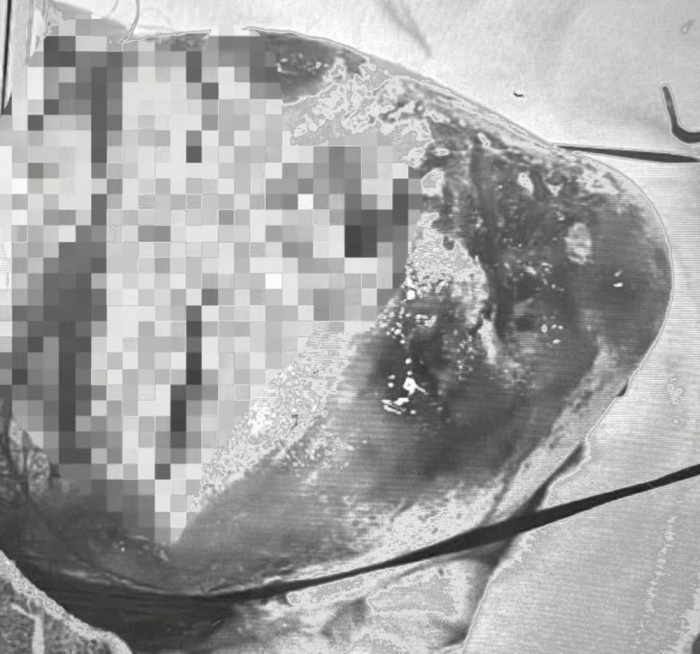

2枚の写真を比べてください。

ひき逃げ事故の被害者・高橋琴さん(仮名)の受傷直後顔面写真。直視するのがつらい写真ではあるが、事故の実態を如実に伝えてくれている

上の写真をモノクロにするとこうなる。だいぶ印象が違う

これは、高橋さんの娘・琴さん(仮名)の受傷直後の写真です。

モザイクをかけていますが、カラーとモノクロ、それぞれの写真が与える印象はいかがでしょう。この写真をイラストにしてみたのが下の画像です。被害の過酷さはもっと薄まるのではないでしょうか。